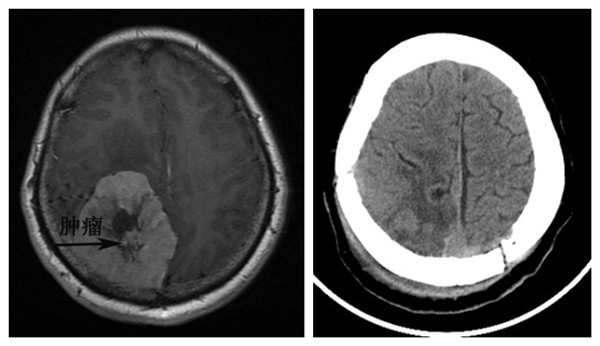

术前磁共振,提示右侧顶枕叶巨大肿瘤 术后CT,提示肿瘤已切除

日前,西安交通大学第二附属医院神经外科完成一例颅内巨大肿瘤切除术。患者文女士在20年前就感到头痛,10年前觉得双眼视力下降,3年前右眼几乎失明,左眼也仅可有光感,在这种情况下,文女士没有采取任何的治疗。5个月前双眼球向外突出,2天前感觉头痛明显加重,伴频繁呕吐,这时文女士才觉得病情比较严重,到医院一查头颅CT,发现颅内长了一个拳头样大小的肿瘤,最大直径达到了7cm,压迫脑组织,引起了脑组织水肿,移位。